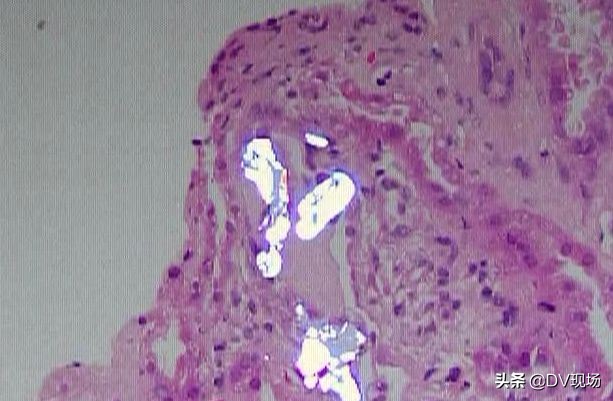

喝了杨桃酒,怎么会引起肾衰竭?罪魁祸首便是它!杨桃里面的有毒成分——草酸,“短期大量摄入杨桃,杨桃里的有害成分草酸会进入血液,沉积在肾脏,形成结晶;从而阻塞肾小管,对肾脏其他细胞产生炎症反应。另外,患者喝的杨桃酒,浸泡了两三年,时间比较长;草酸盐更容易析出来,更容易溶到酒里面,引起中毒。”